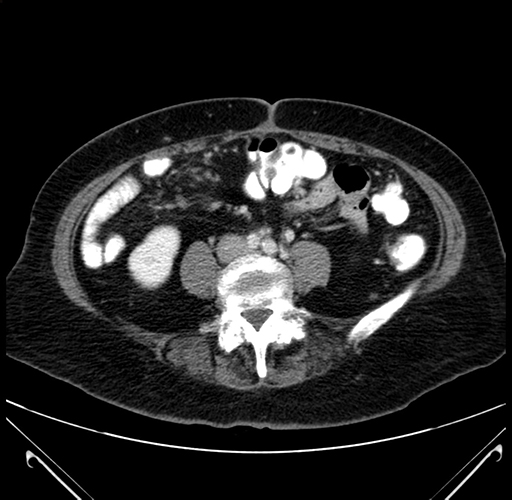

Pre-Chemo: Axial Venous

Axial Venous